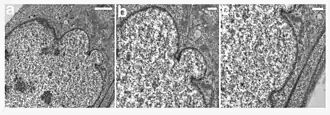

Ultrastructural analysis of the nuclear envelope in fibroblasts from a subject with HGPS. Low magnification transmission electron microscopic image of a passage 10 PT001 nucleus showed several herniations (a). Two higher-magnification images of the same nucleus at sites of blebs (b and c) showed a close apposition of the chromatin to the nuclear envelope. In a, b, and c, the nucleus is to the left. Scale bars correspond to 2 μm in panel a, and 500 nm in panels b and c.

HGPS is caused by mutations that weaken the structure of the cell nucleus, making normal cell division difficult. The histone mark H4K20me3 is involved and caused by de novo mutations that occur in a gene that encodes lamin A. Lamin A is made but is not processed properly. This poor processing creates an abnormal nuclear morphology and disorganized heterochromatin. Patients also do not have appropriate DNA repair, and they also have increased genomic instability.[14]